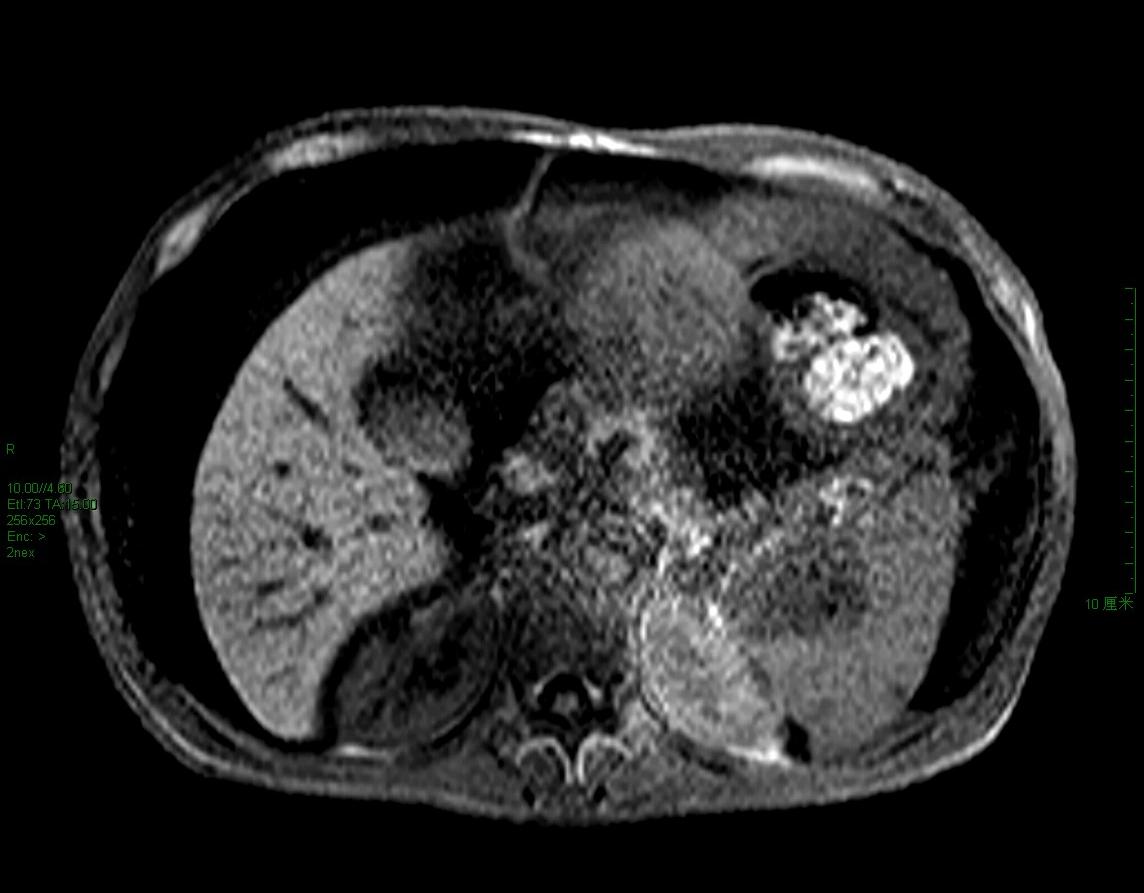

脾脏占位

大量腹水、脾门占位(长t1短t2为主混杂信号)------考虑为恶性肿瘤伴腹膜转移、腹水合并感染。

但脾脏占位不好解释